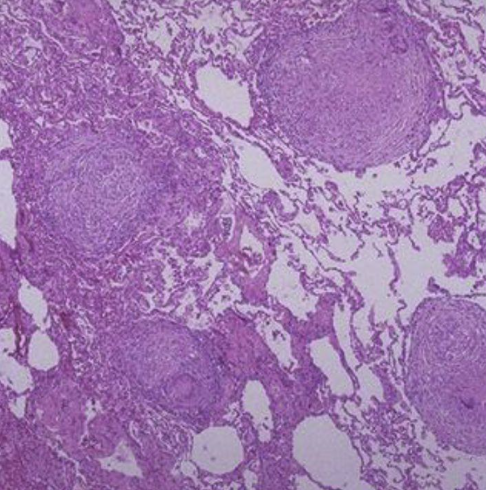

lymphoid follicles and germinal centres in the lung! Usual interstitial pneumonia (UIP) pattern